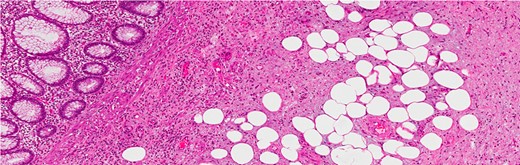

Histological examination showed an appendix measuring 7 cm in length and 0.8 cm in diameter with a cystic lesion at the base measuring 3.5 × 2.5 cm2. It had a grey homogenous cut surface invading the appendix wall while the mucosa was unremarkable. The mucosal lining showed elongated and dilated tubules with Goblet cell proliferation with no evidence of dysplasia. The sub-mucosa displayed an area of extensive edema, vascular congestion with focal hemorrhage and abundance of spindle cells, dispersed in a loose fibromyxoid stroma. The sub-mucosal background had copious eosinophils, lymphocytes and blood cells. There was no mitosis, acute inflammation, granuloma, ischemia or vasculitis (Figs 3–6). These findings are consistent with an appendicular IFP (Vanek’s tumor).

(a) H&E stain of a lesion in the appendiceal wall with infiltrative nature (intermediate power). (b) H&E stain of abundant spindle cell, dispersed in loss fibromyxoid stroma, infiltrating the fat (high power).

Infiltration into the sub-mucosa of the appendix (H&E stain, high power).